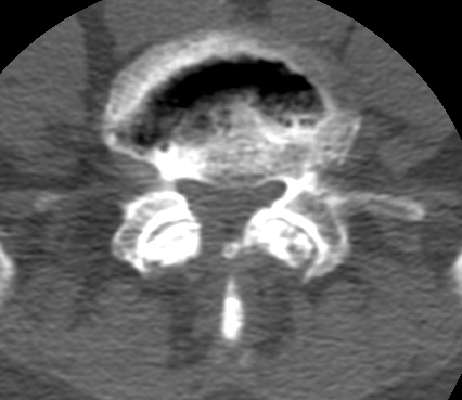

Diagnosis:Degenerative disk disease Discussion:The presence of a linear radiolucency in the disk space (vacuum phenomenon) is a typical finding of degenerative disk disease. It is often associated to other findings of degenerative disk disease such as disk space narrowing and endplate sclerosis. Gas in the disk space is rarely associated to disk space infection. References: